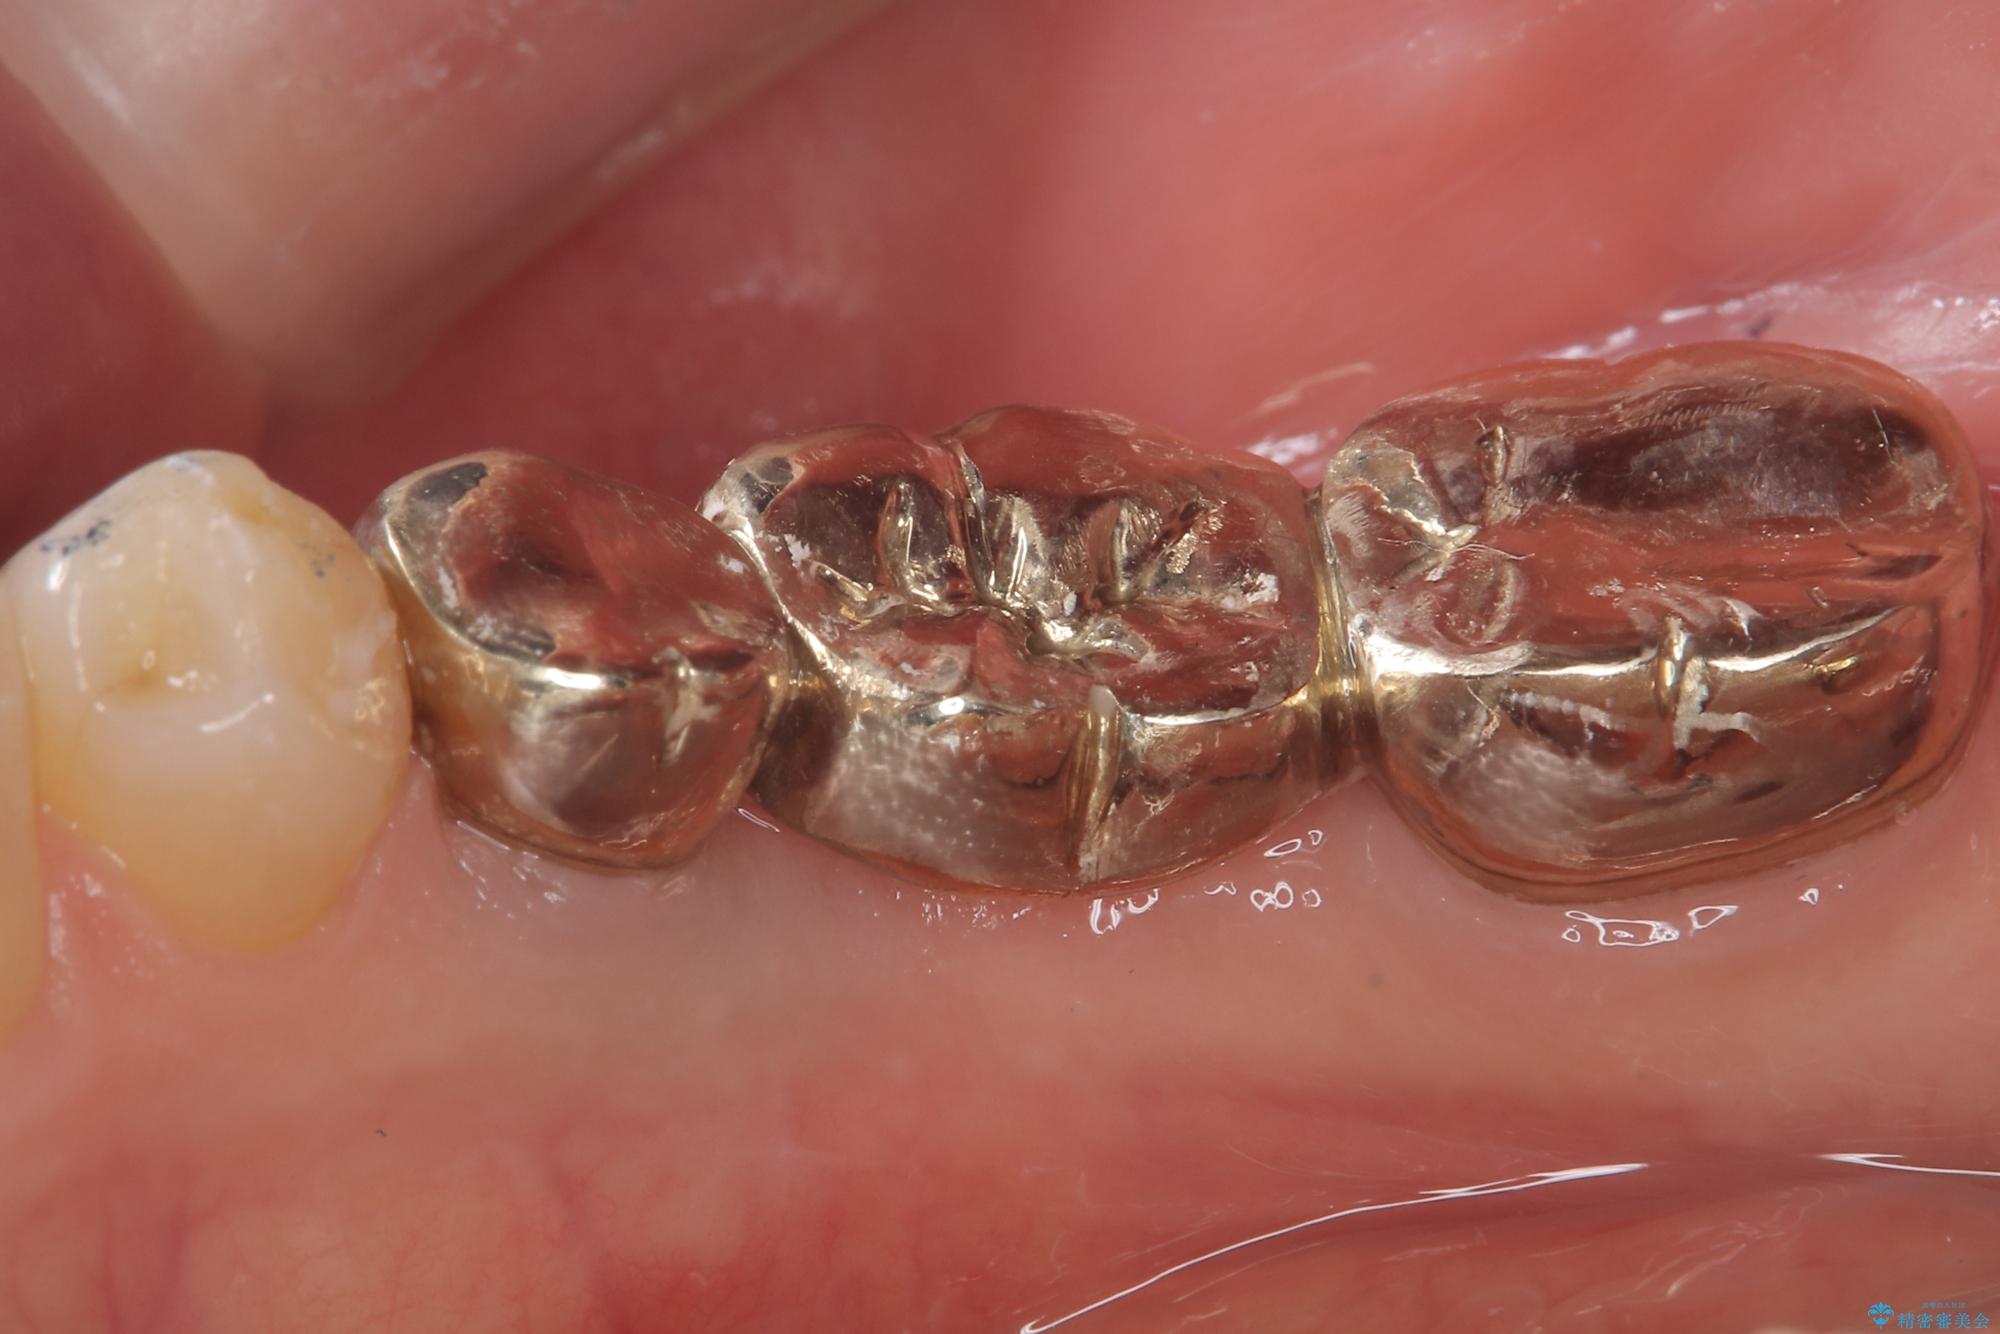

セラミックに比べ、割れづらい金属(ゴールドでのブリッジのやり替えとなりました。

セラミックに比べ、破折リスクの少ない金属を使用したブリッジでのやり替えとなりました。

PGA(ゴールド)クラウン、インレーの注意事項(リスク・副作用など)

- インレーおよびクラウンは脱離するリスクがあります

- 形成量はセラミックより少ないですが、歯の形成、修復後に歯に症状が出ることがあります